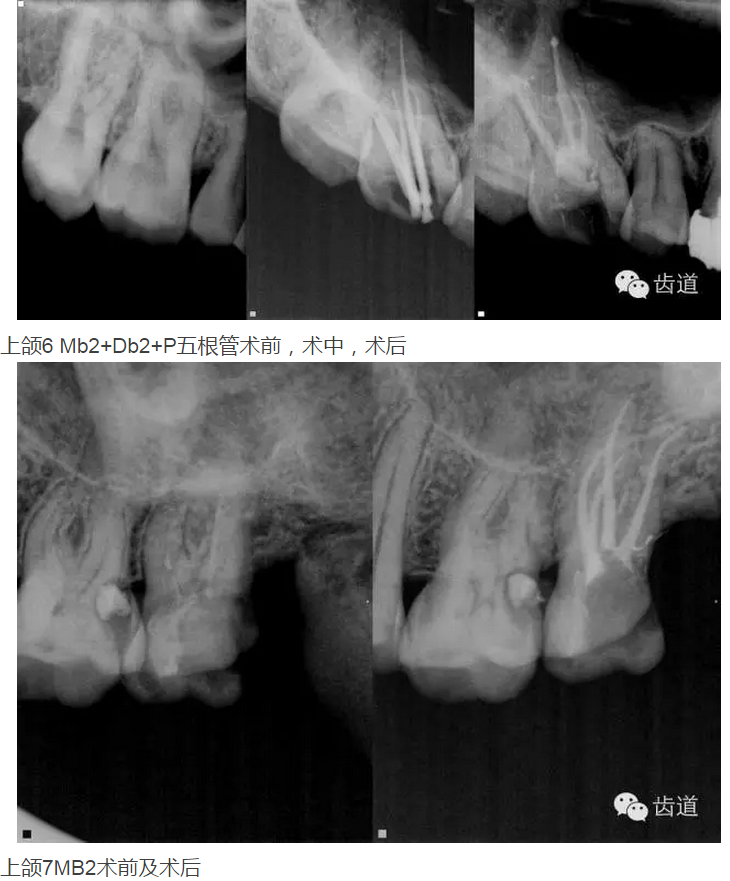

上頜第一磨牙:多為3-4個(gè)根管,MB2發(fā)生率約為60%;

上頜第二磨牙:與上頜第一磨牙相似,多為3根管,偶見雙鄂根管;